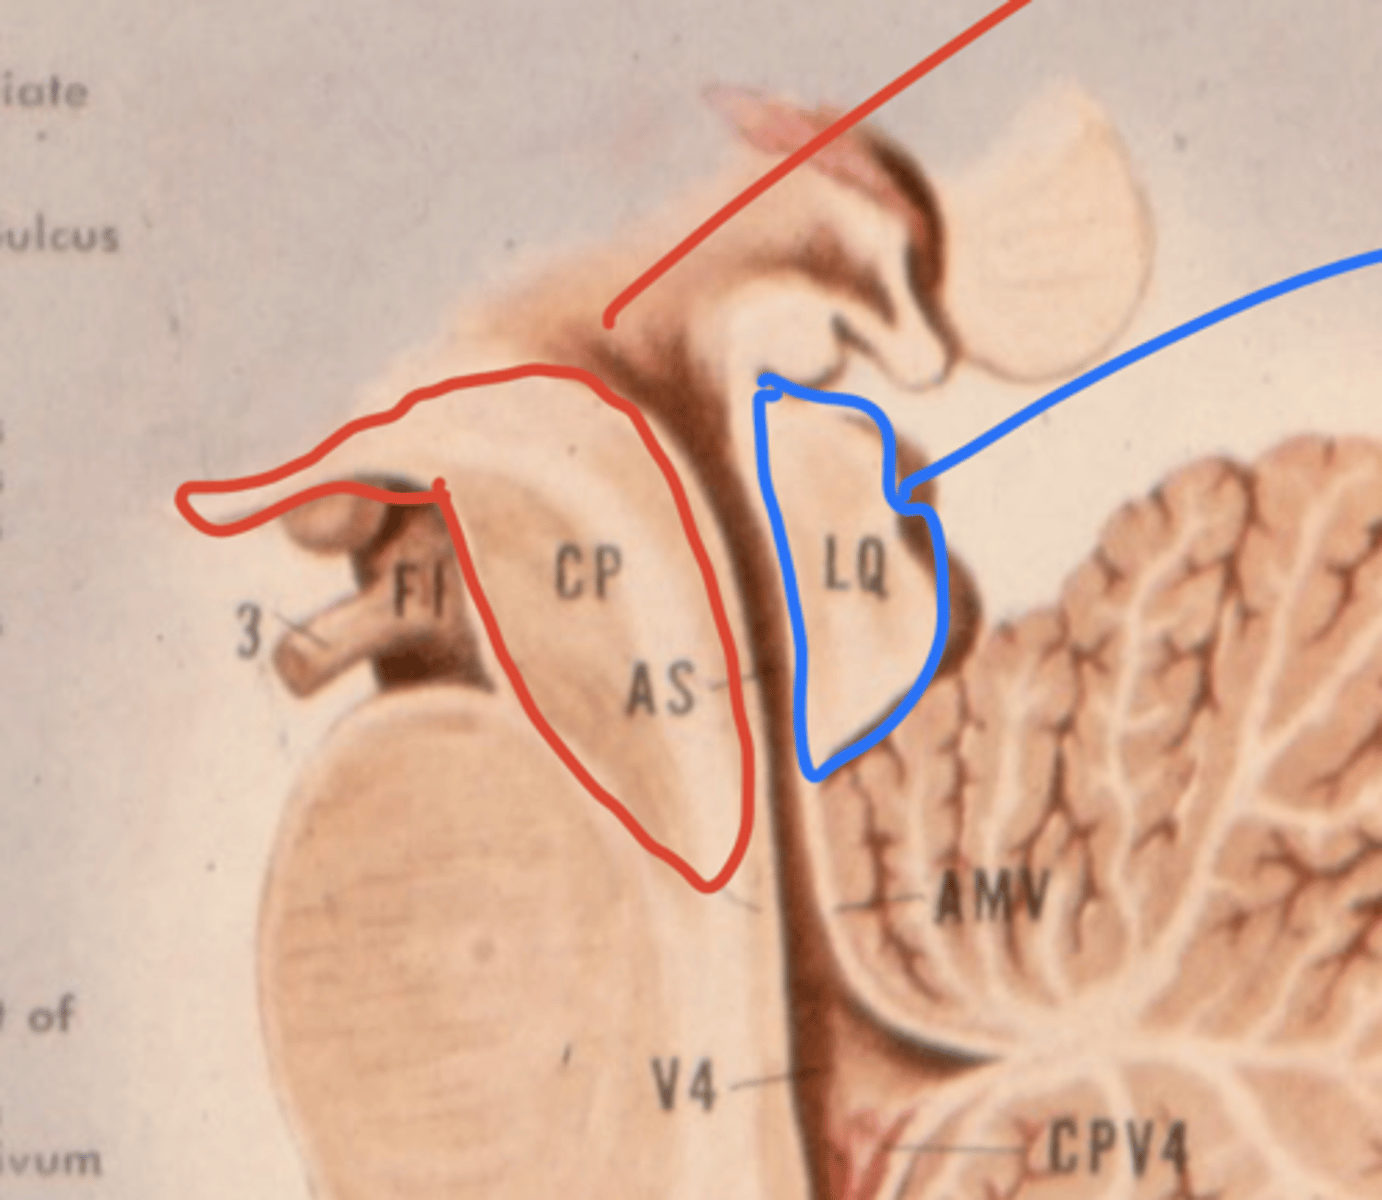

What is the tectum?

roof of the midbrain

What is the tegmentum?

floor of midbrain

What are the fibers of the tegmentum?

ascending fibers

What is the crus cerebri?

part of the cerebral peduncles which contain descending tracts

What are the fibers of the crus cerebri?

descending fibers

What leaves the peduncular fossa?

CN III

What notable structures are on the dorsal surface of the mesencephalon (tectum)?

1. superior colliculi (right and left)

2. inferior colliculi (right and left)

image -- 5

What other notable structure should you see if you see two red nuclei?

"if you see two red nuclei you're at the superior colliculus level"

Where does CN III exit the brainstem?

interpeduncular fossa (ventral surface)

Where does CN IV exit the brainstem?

inferior colliculus (dorsal surface)

exits dorsal + caudal (posteroinferior) to nucleus

Where are the CN III and IV nuclei?

tegmentum mesencephalon

CN III -- anterosuperior

CN IV -- posteroinferior